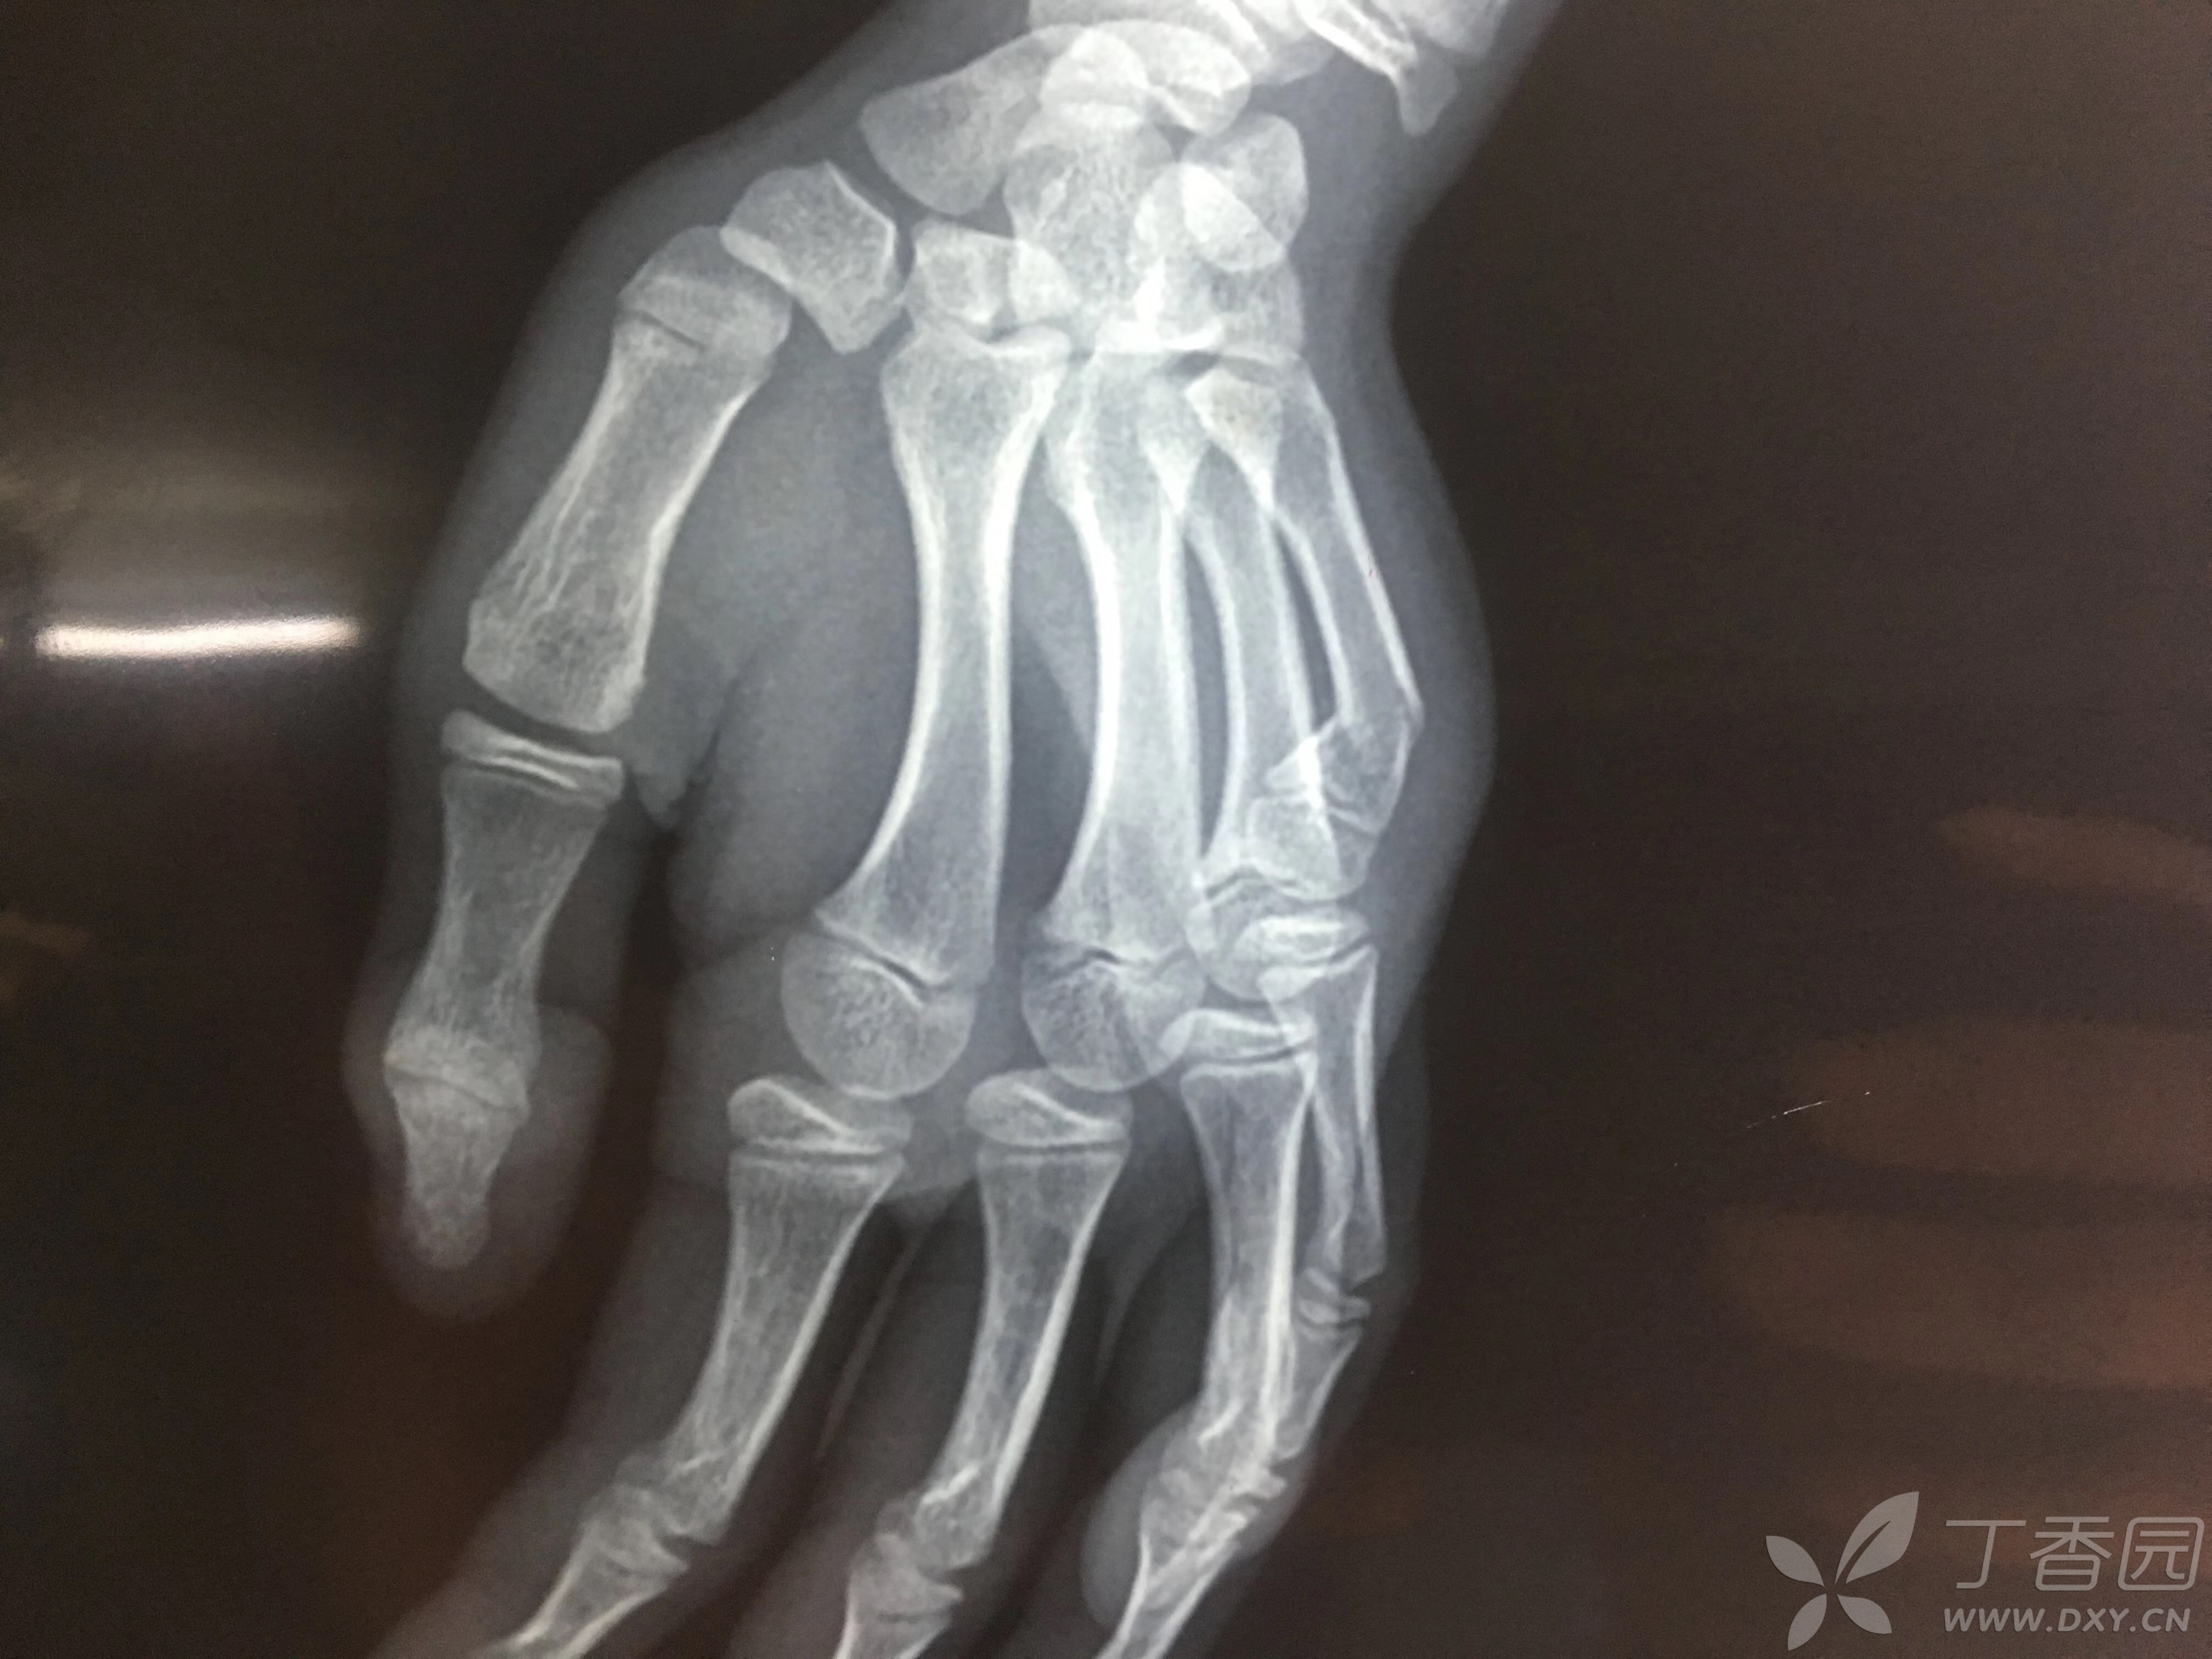

拳击手骨折boxer's fracture▼

拳击手骨折(第四掌骨骨折),请医生看看需要做手术吗?